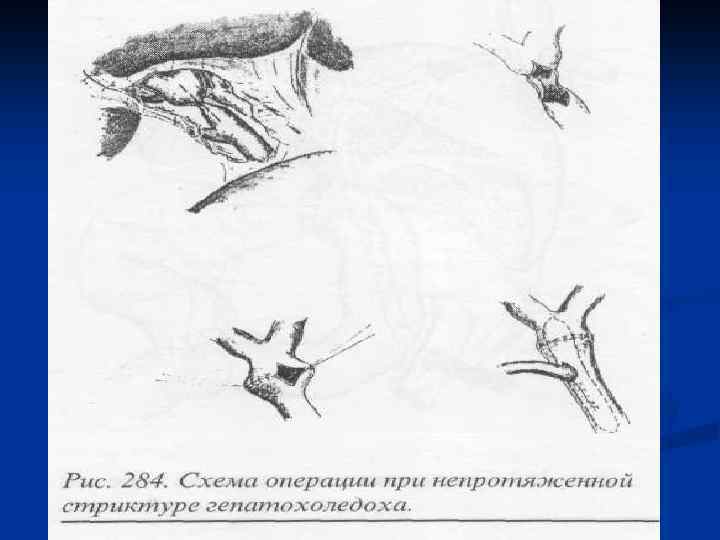

I. Восстановительные операции (восстановление проходимости протоков) 1. Эндобилиарные вмешательства под УЗИ или R – контролем (бужирование, баллонная дилатация, стентирование протоков). 2. Пластика стриктуры 3. Иссечение стриктуры с наложением анастомоза. II. Реконструктивные операции (наложение билиодигестивных анастомозов) 1. Анастомозы внепеченочных желчных протоков: а) с двенадцатиперстной кишкой (ХДА) б) с тощей кишкой (гепатико-, холедохоеюноанастомозы по Ру или по Брауну). 2. Анастомозы внутрипеченочных желчных протоков с сегментом тощей кишки, выключенной по Ру или желудком при высоких стриктурах

I. Восстановительные операции (восстановление проходимости протоков) 1. Эндобилиарные вмешательства под УЗИ или R – контролем (бужирование, баллонная дилатация, стентирование протоков). 2. Пластика стриктуры 3. Иссечение стриктуры с наложением анастомоза. II. Реконструктивные операции (наложение билиодигестивных анастомозов) 1. Анастомозы внепеченочных желчных протоков: а) с двенадцатиперстной кишкой (ХДА) б) с тощей кишкой (гепатико-, холедохоеюноанастомозы по Ру или по Брауну). 2. Анастомозы внутрипеченочных желчных протоков с сегментом тощей кишки, выключенной по Ру или желудком при высоких стриктурах